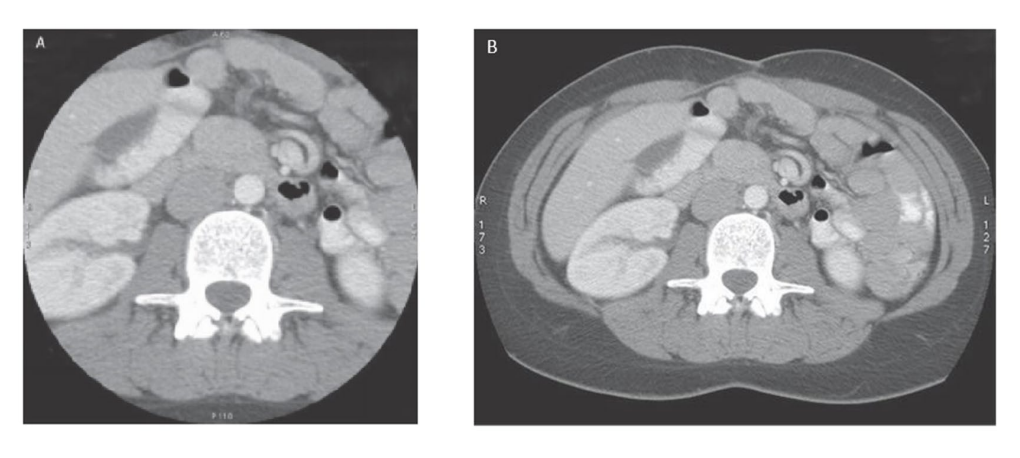

What are MIPs

- Maximum Intensity Projections - examines each voxel along a line from the views eyes and selects only the highest values to be displayed - used when objects of interest are the brightest objects in the image (bones and contrast filled structures)